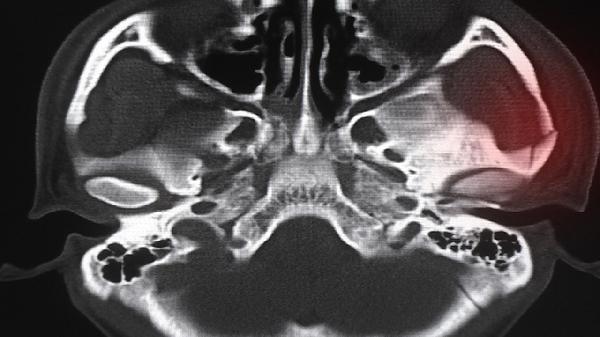

补骨脂、骨碎补等成分可刺激成骨细胞活性,延缓软骨退化进程。针对X线显示关节间隙狭窄但未达到手术指征的早期骨关节病患者,可帮助维持关节功能。